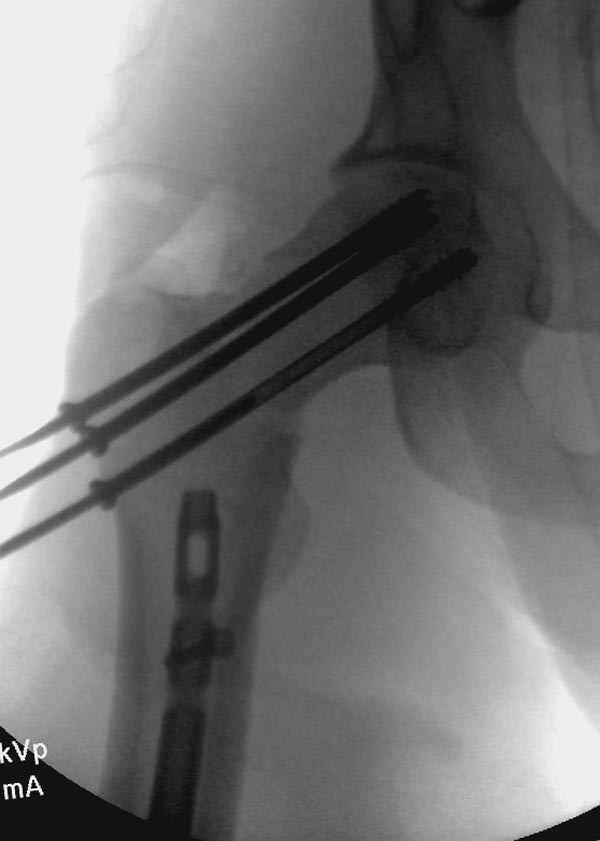

Пока надо делать снимки в классических укладках, т.е. хотя бы в двух проекциях. А по тактике из всех переломов: шейка является приоритетным и ургентным. Идеально фиксировать канюлированными винтами, но усложняется тем, что имеется перелом верхушки вертела. Навряд ли получится закрыто, надо открывать. Все зависит от возможностей на месте (писали насчет DHS), можно и интрамедуллярный гвоздь, но не надо укорачивать, только пустить overlapping, т.е. пластина от DHS покрывает часть гвоздя.

Здесь выставлен ренгенограммы больного, ему 21, травму получил в результате высокоскоростной погони на украденной машине, которая закончилась смертью трех остальных “боевых комрадов”. Начатую коллегой открытую операцию на шейке пришлось закончить мне, установкой винтов и ретроградной фиксацией бедра. Выписка в обычное сроки и наблюдался амбулаторно. Каждый раз напоминали о возможности осложнений ввиде несращения! По истечению 4 месяцев появились признаки варусной деформации. На СТ срезах несращение шейки и бедра. Риминг, замена на более толстый гвоздь и вальгусная остеотомия.